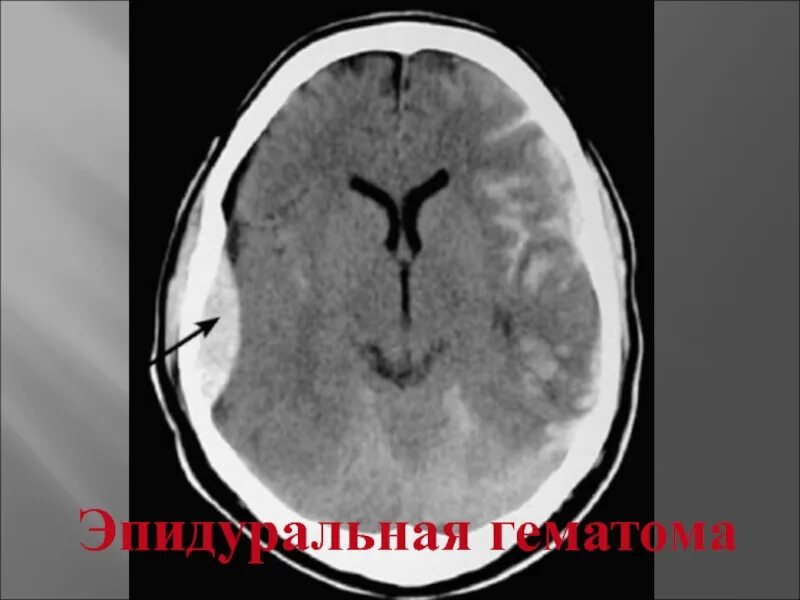

Как отличить гематому